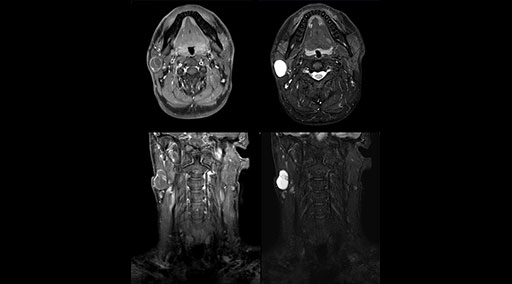

“Without using an endorectal coil we do our prostate MR at 0.5 mm resolution, following the European society of urology protocol [1]. For certain joints we use a virtual arthroscopy protocol with 1 mm pixel size and 2 mm slice thickness. Ingenia really excels in our neurography, brachial plexus and prostate scans. Our neurologists insist on using our 3.0T for those,” Dr. Kaakaji adds.

“Our DMG Lisle location includes a cancer center, so soft tissue neck scans, brachial plexus scans, and prostate scans are common. For these exams, mDIXON TSE provides excellent images with and without fat suppression all while helping us reduce repeats and work more efficiently,” Mr. Duffy says.